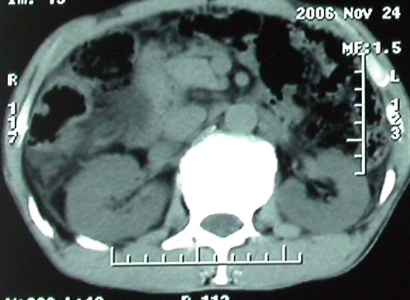

标题: CT5432:上腹隐痛、饱胀、消瘦2-月(尾状叶肝癌)。 [打印本页]

标题: CT5432:上腹隐痛、饱胀、消瘦2-月(尾状叶肝癌)。

男,57岁。

平扫